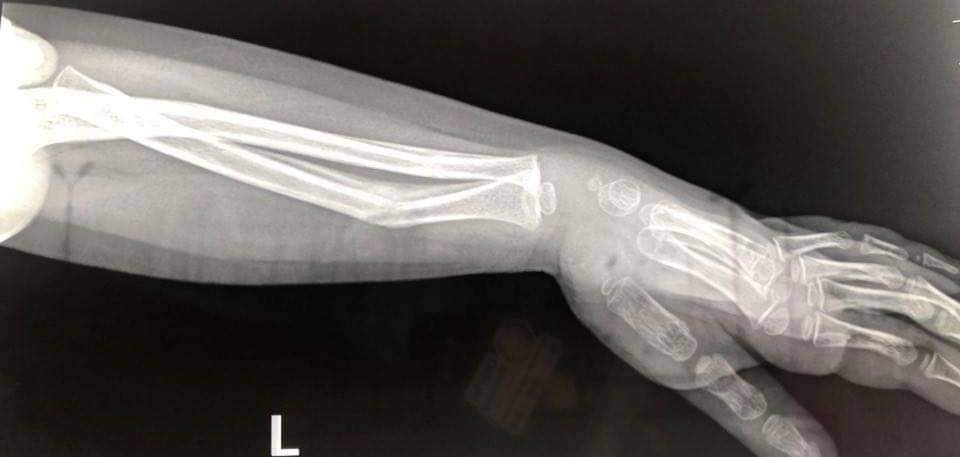

În radiografia de la externare se vede foarte clar că oasele nu erau poziționate și s-au ghipsat prost. Toate lucrurile astea n-ar fi trebuit să se întâmple, spune Paula Niculescu.